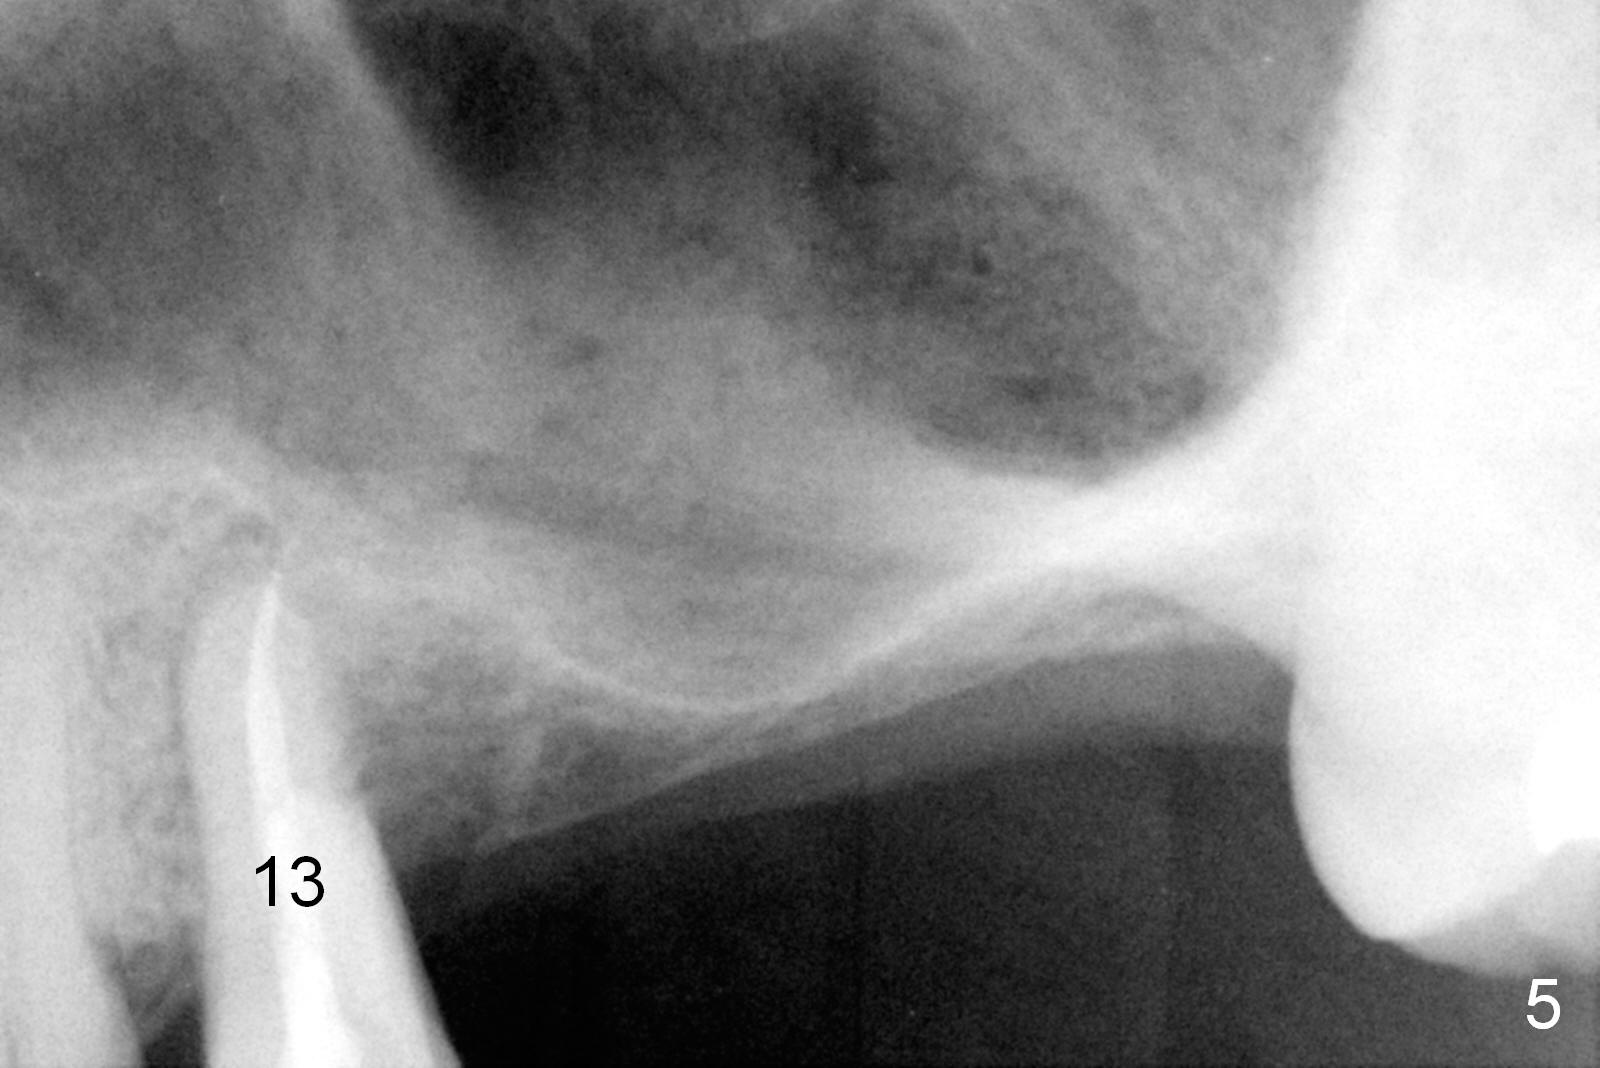

A 45-year-old man has lost #14 and 15 for a while. The sinus floor is 2-3 mm (Fig.1 (CBCT sagittal section), 2,3 (coronal sections)). The sinus membrane will be lifted by lateral window approach (Fig.2,3). With Metronidazole (prevent postop sinus infection) and 2% Xylocaine 1:50,000 gauze inserted underneath the sinus floor, osteotomy is initiated from the crest using UF cassette drills. Two of 5-6.5x8 mm implants will be placed, followed by immediate cemented abutments. Pack bone graft before and after implantation. Prepare both a syringe of Osteogen and allograft. The splinted immediate provisional will strengthen primary stability of the implants (Fig.4). The distal root caries of #13 (Fig.1 *) has been fixed as well as root canal therapy (Fig.5).